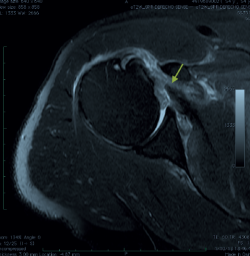

La evaluación radiológica incluyó una resonancia magnética (RM) preoperatoria del hombro afectado y la revisión de forma independiente por parte del cirujano. La RM se utilizó para confirmar el diagnóstico (Figura 1), clasificar la rotura según la escala de Lafosse, evaluar la retracción del tendón, la infiltración grasa (clasificación de Goutallier) en el plano sagital, descartar cambios degenerativos avanzados y evaluar la patología asociada del bíceps (Figura 1).

Figura 1. Imagen axial por resonancia magnética de una rotura subescapular aguda de espesor completo. Flecha: rotura del tendón subescapular.